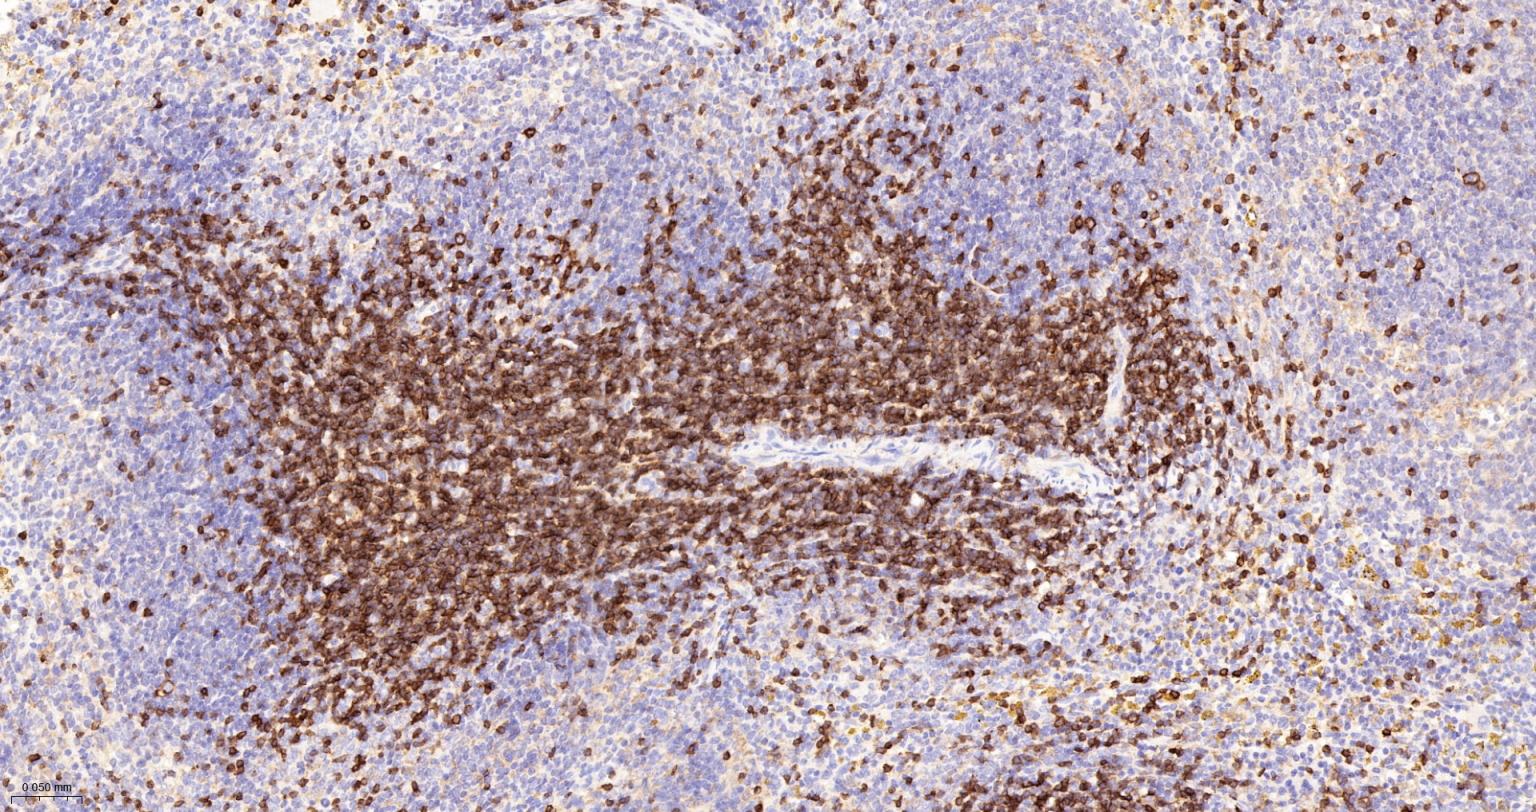

IHC-PHuman, Mouse, Rat1:500-2000

IHC-FHuman, Mouse, Rat1:500-2000